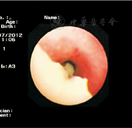

支气管镜下53例均可见支气管黏液栓,见图1、图2、图3;黏液栓成支气管树样塑型19例(35.85%),见图4、图5。17例支气管黏液栓和支气管塑型行病理检查,均为假膜样炎性坏死组织,可见大量中性粒细胞及淋巴细胞浸润,少量巨噬细胞及嗜酸性粒细胞,见图6。

影像学多表现为大灶性肺炎、节段性肺炎、肺实变或肺不张,炎症累及多达两叶以上,患儿发生胸腔积液等肺外并发症,提示肺内病变范围较大、损害程度较重,也是发生后遗症的危险因素[20]。支气管镜下多可见条索状黏液栓塞,部分呈支气管树样塑型堵塞支气管开口。本研究资料中大部分黏液栓堵塞两个或两个以上开口,以右肺上叶支气管分支内黏液栓塞较多见,考虑与咳嗽时上叶受力较小,黏液栓不易咳出,及右上肺含气量相对较少,通气状况差,易引起炎症等有关。文献报道支气管黏液栓堵塞严重可危及患儿生命,若清除延迟可导致支气管扩张、闭塞性支气管炎等。支气管镜下支气管黏膜表现为充血水肿、滤泡增生、糜烂坏死甚至管腔开口炎性狭窄[21]。研究显示支气管管腔开口炎性狭窄、黏液栓塞需警惕难治性及迁延性MPP可能[22]。